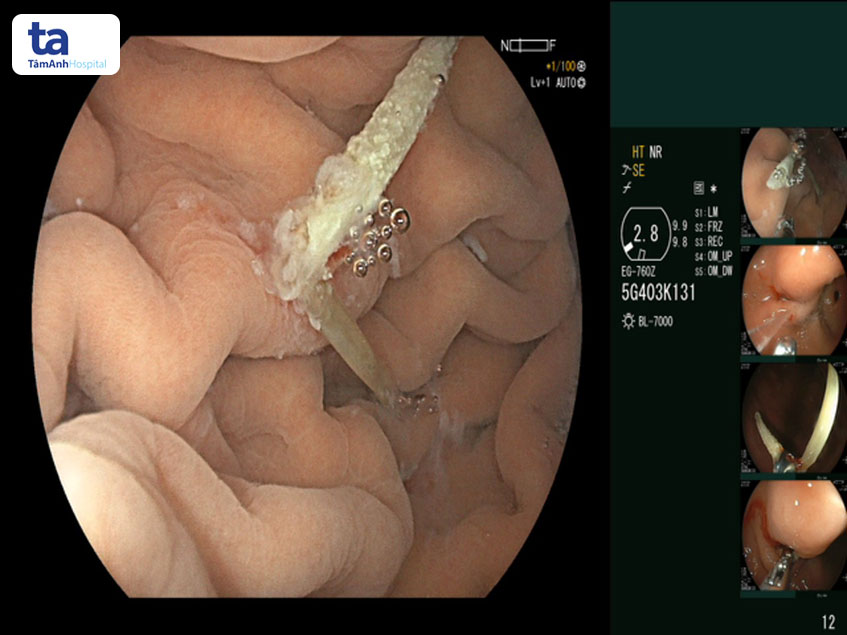

TS.BS Đỗ Minh Hùng cho biết: “Khi nội soi cho bệnh nhân, thành dạ dày sạch, không có dấu hiệu xuất huyết, viêm loét. Tuy nhiên, tại bờ cong dạ dày, đoạn sát gan có lồi lên đốm mủ trắng. Khi dùng dụ cụ bơm rửa, tôi đã phát hiện dấu vết xương tại đây và gắp dị vật thành công trong vòng 5-7 phút. Dị vật được xác định là xương cá, nhọn và dài 3cm. Trường hợp bệnh nhân nuốt dị vật đâm thủng dạ dày, xuyên qua gan, đi qua 2 cơ quan như trường hợp bệnh nhân này rất hiếm gặp.